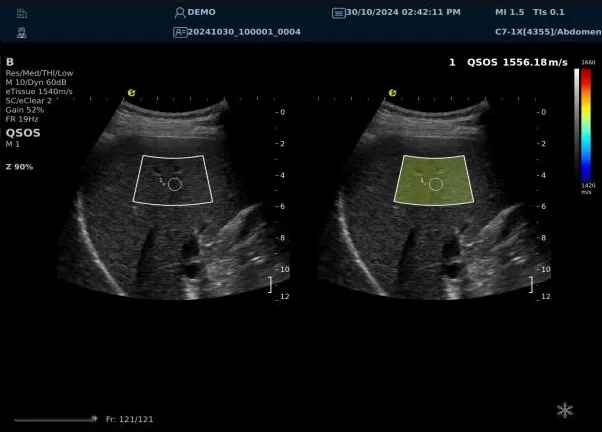

640.jpg123 (2).jpg可以设想,单位时间可发射的脉冲波越多、单位面积可发射的脉冲波越密集,得到的数据结果就越快、越多。也就是说,如果医生希望得到实时、大幅的声速定量图像,就需要超声系统具备“超快速”发射和接收的能力,利来国国际网站医疗(ESI)ePascal东风系列超声平台的200+倍成像速度,成为了这项新技术得以临床应用的重要条件。

以上为应用声速定量成像技术检查肝脏的超声图像,图中在取样框内选择了三个测量区域,得出了各区域内的组织声速值以及声速衰减系数等结果。